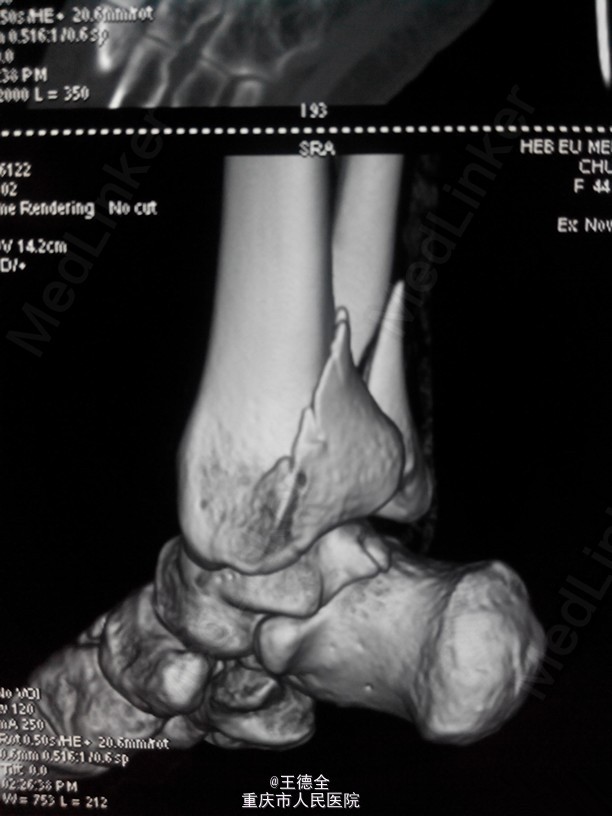

外踝及后踝骨折一例

患者女,44岁,车祸致右踝关节疼痛,肿胀,活动受限入院。肿胀消退后于手术治疗,选择后外侧入路做一个切口,克氏针临时固定,最终钢板固定。